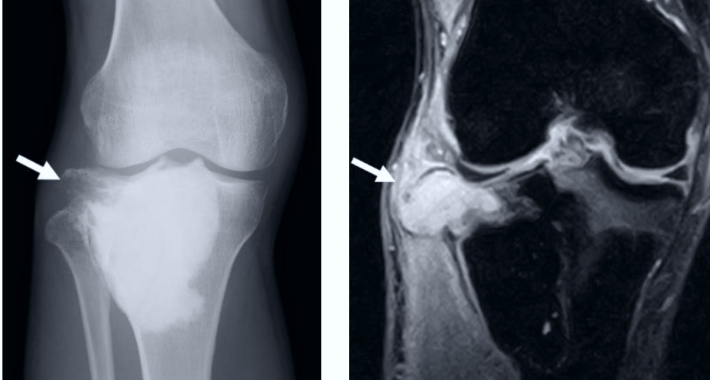

- Рентгеновский снимок. В этом тесте используется небольшое количество радиации для создания изображений тканей, костей и органов на пленке.

- МРТ. Это тест, в котором используются большие магниты, радиоволны и компьютер для получения детальных изображений тканей тела. Этот тест также может исключить любые проблемы со спинным мозгом и нервами.